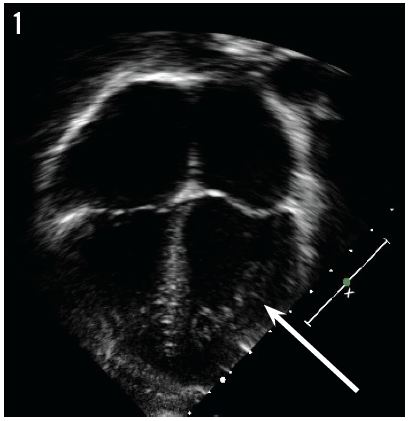

Tamika Rozema, MD; Lindsay Ragsdale, MD; Kimberly Northrip, MD, MPH

When she was 4 months old, a girl presented to her primary care pediatrician with a history of “passing out.”